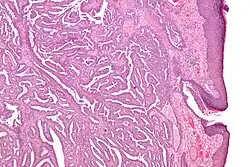

Micrograph of a nipple adenoma. H&E stain.

Once excised, the macroscopic appearance of nipple adenomas is of a poorly defined nodular mass. The microscopic appearance can be quite bizarre, and may be misinterpreted as a carcinoma. Nipple adenomas usually have a rounded outline at low magnification, and at higher magnification can be seen to consist of a haphazardly arranged mass of proliferating tubular structures composed of epithelial and myoepithelial cells within varying amounts of fibrous stroma. The epithelial cells are usually columnar, but the columnar epithelial cells can undergo apocrine or squamous metaplasia. Mitotic figures and necrosis are not commonly seen.[1]